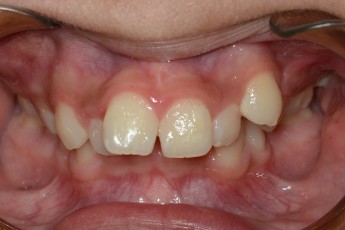

BEFORE & AFTER